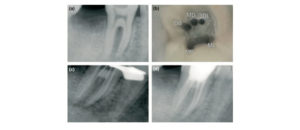

La reabsorción cervical invasiva (RCI) es una complicación patológica grave, una forma poco frecuente y a menudo agresiva de reabsorción radicular externa que incluye dientes